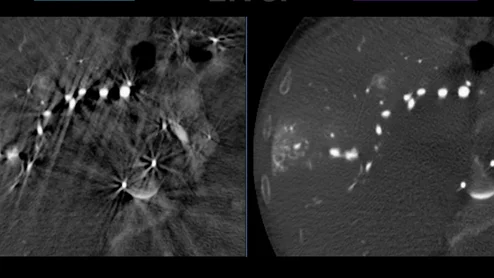

cvi42 | Plaque Circle Cardiovascular Imaging

The use of AI to evaluate plaque buildup in CCTA images has been one of cardiology’s biggest ongoing trends. Implementing this software into existing workflows, however, can be a challenge. An upcoming webinar is focused on providing guidance to hospitals and cardiology practices hoping to learn more about this topic.